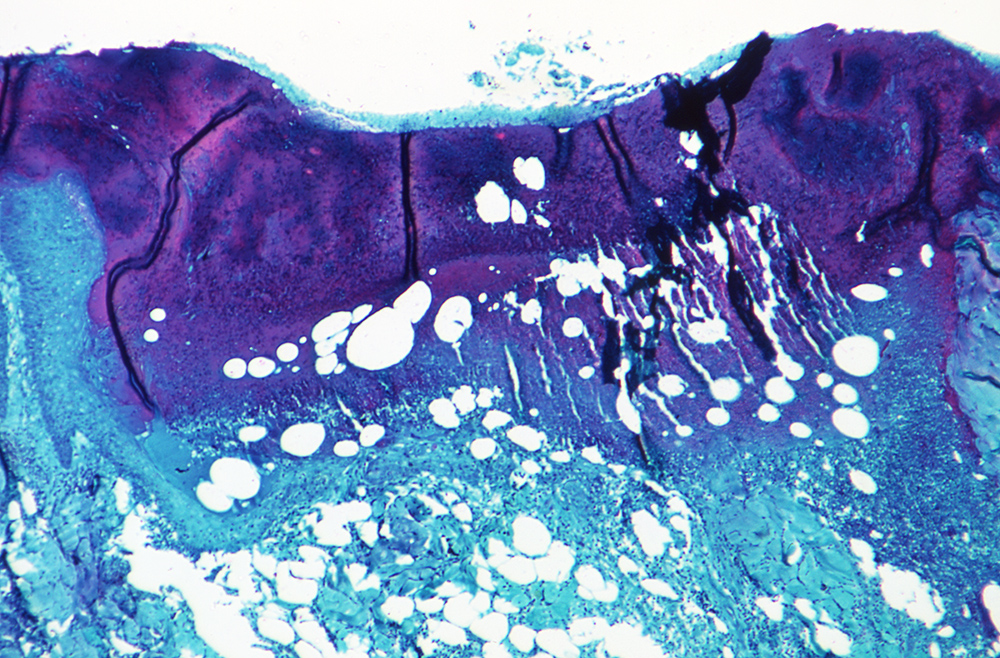

猴痘(Monkeypox)首次发现于1958年,当时在用于研究的猴子群体中暴发了两次类似痘的疾病,因此得名“猴痘”。第一例猴痘的人类病例是在1970年刚果民主共和国的一名儿童身上发现的。作为一种病毒性人畜共患病,猴痘在人类中出现的症状类似天花,但病情较轻。不过与已经消失的天花不同,猴痘仍在非洲部分地区散发。